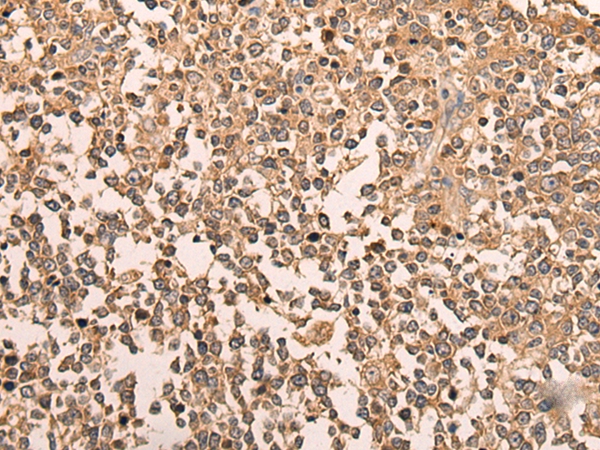

The image on the left is immunohistochemistry of paraffin-embedded Human tonsil tissue using 46596(LDAH Antibody) at dilution 1/70, on the right is treated with synthetic peptide. (Original magnification: x200)